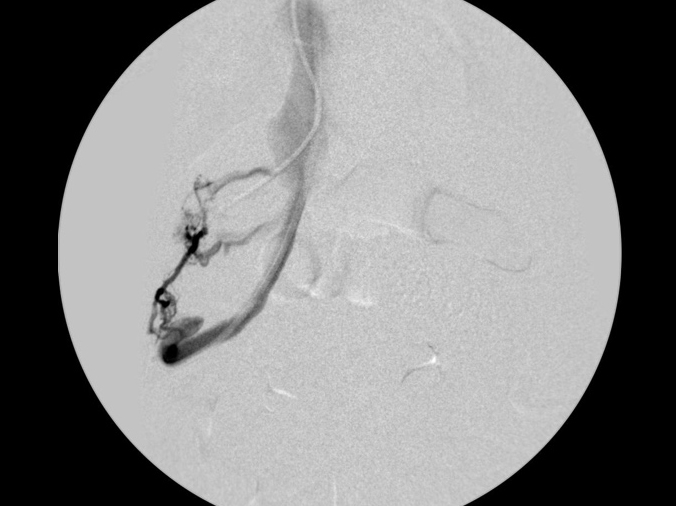

カテーテルでのシャント血管の造影検査